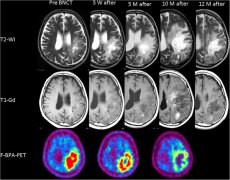

BNCT硼中子俘获治疗间变型星形细胞瘤实例解析

一名44岁男性的颅骨切开术显示间变性星形细胞瘤。他接受了标准放化疗(XRT 60 Gy与TMZ)。不幸的是,病变由于失语症加重和右偏瘫而复发,这迫使他退出工作。...